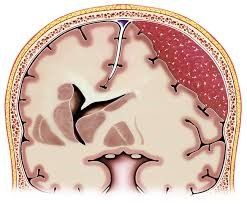

Субдуральная гематома диагностика